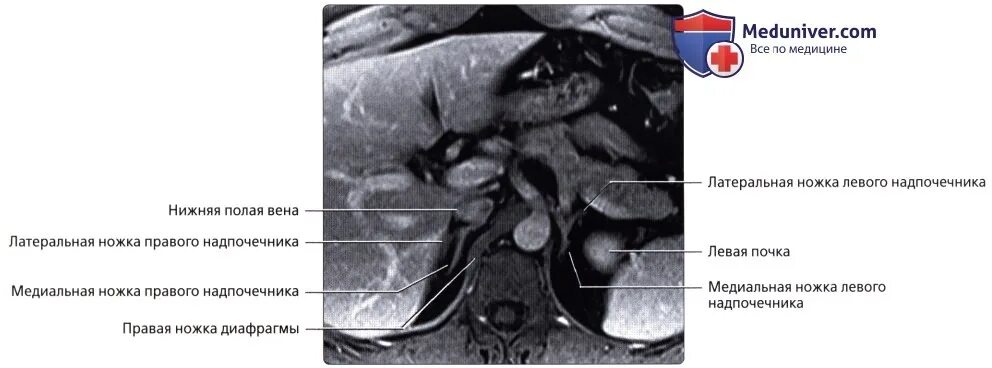

Надпочечник не визуализируется что это значит